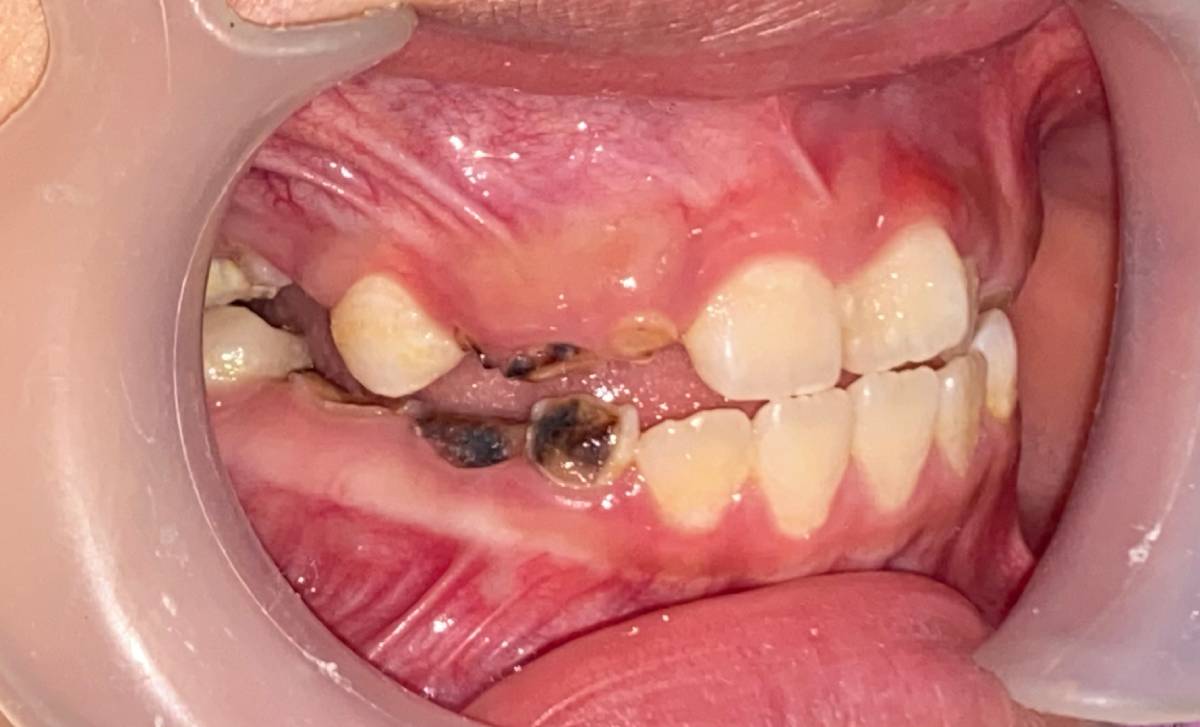

Đường là nguyên nhân hàng đầu gây sâu răng ở trẻ em. Khi trẻ ăn quá nhiều bánh kẹo, socola, nước ngọt hoặc đồ uống có gas, lượng đường trong khoang miệng tăng cao. Vi khuẩn sẽ chuyển hóa đường thành axit, làm mòn men răng và hình thành lỗ sâu.

Bên cạnh đó, đồ uống có gas chứa axit mạnh, có thể làm bào mòn men răng, khiến răng yếu và dễ gãy.

Vệ sinh răng miệng là thói quen bắt buộc để giữ răng khỏe mạnh. Nếu trẻ lười đánh răng hoặc đánh răng sai cách, mảng bám sẽ tích tụ, dẫn đến:

-

Sâu răng và viêm nướu.